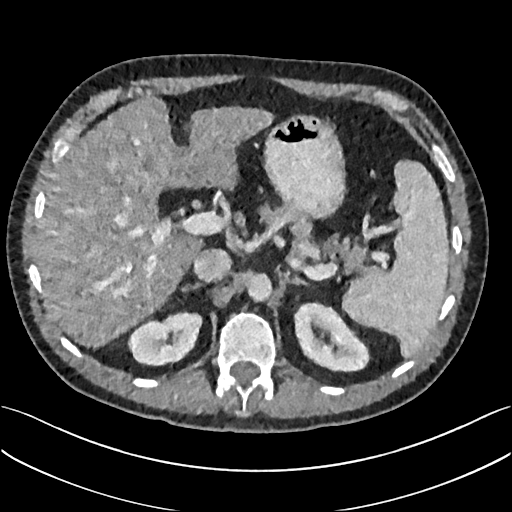

To demonstrate the effectiveness of the proposed network, we perform the qualitative comparisons over three representative abdominal images presented in Figs. 3, 5 and 7. For better evaluations of the image quality with different denoising models, zoomed regions-of-interest (ROIs) are marked by red rectangles and shown in Figs. 4, 6 and 8 respectively. Note that all results from different denoising models focus on two aspects: content restoration and noise-reduction. All CT images in axial view are displayed in the angiography window [-160, 240]HU.

The real NDCT images and corresponding LDCT images are presented in Figs. 3a and 3b. As observed, there are distinctions between ground truth (NDCT) images and LDCT images. Figs. 3a and 7a show the lesions/metastasis. Fig. 5a presents focal fatty sparing/focal fat. In Figs. 4a, 6a and 8a, these lesions can be clearly observed in NDCT images; in contrast, from Figs. 4b, 6b, and 8b, it can be seen that the original LDCT image is noisy, and lacks structural features for task-based clinical diagnosis. All adopted denoising models suppress noise to some extent.

From Figs. 7 and 8, we can see mean-based and SL-based methods work well with effective noise suppression and artifact removal. However, the illustrations in Fig. 8 show that these methods blur the local strutural features. Our proposed SMGAN-based methods present a better edge preservation than the competing methods.

Overall, the observations above support the following statements. First, although the voxel-wise methods show good noise-reduction properties, to some extent they blur the contents and lead to the loss of structural details because they optimize the results in the voxel-wise manner. Second, SL-based methods better preserve texture than mean-based methods, but they cannot preserve overall image intensity. Third, the results produced by the proposed SMGAN-3D demonstrate the benefits of the combination of two loss functions and the importance of the adversarial training [41, 42].

III-D2 Comparison with WGAN-based denoising methods

To evaluate the effectiveness of our proposed objective function, we compare our method with existing WGAN-based networks, including WGAN and WGAN-VGG. Considering the importance of clinical image quality and specific structural features for medical diagnosis, we adopted the adversarial learning method [41, 42] in our experiments because WGAN could help to capture more structural information. Nevertheless, based on our prior experience, utilizing WGAN alone may yield stronger noise than other selected approaches, because it only maps the data distribution from LDCT to NDCT without consideration of local voxel intensity and structural correlations. The observations demonstrate that the noise texture is coarse in the images, as shown in Fig. 4g and Fig. 8g, which support our intuition.

In Figs. 7 and 8, it can be found that the SMGAN-based methods can achieve better anatomical feature preservations and visual quality than other state-of-the-art methods.

The experimental results demonstrate that our proposed objective function is essential to capture more accurate anatomical details.

III-D4 Comparison with 2D-based SMGAN network

In order to evaluate the 3D structural information, we compared SMGAN-3D with SMGAN-2D. As shown in Fig. 4l, our proposed SMGAN-3D generated the results with better subtle details than SMGAN-2D and enjoys more similar statistical noise properties to the corresponding NDCT images. The reasons why SMGAN-3D outperforms SMGAN-2D are follows. First, SMGAN-3D incorporates 3D structural information to improve image quality. Second, SMGAN-2D takes input slice by slice, thus potentially leading to the loss of spatial correlation between adjacent slices.

Figs. 7 and 8 demonstrate that the SMGAN-3D can be used to provide improved anatomical feature preservation over other state-of-the-art methods.

In summary, we compared our proposed methods with existing methods, and it can be clearly observed that SMGAN-3D achieves robust performance in noise suppression, artifact removal, and texture preservation. Note that we recommend the reader to see ROIs (in Fig. 4 and 6) or zoom in to better evaluate our results. To further validate the generalization ability of our proposed model, we conclude more details in Appendix A.